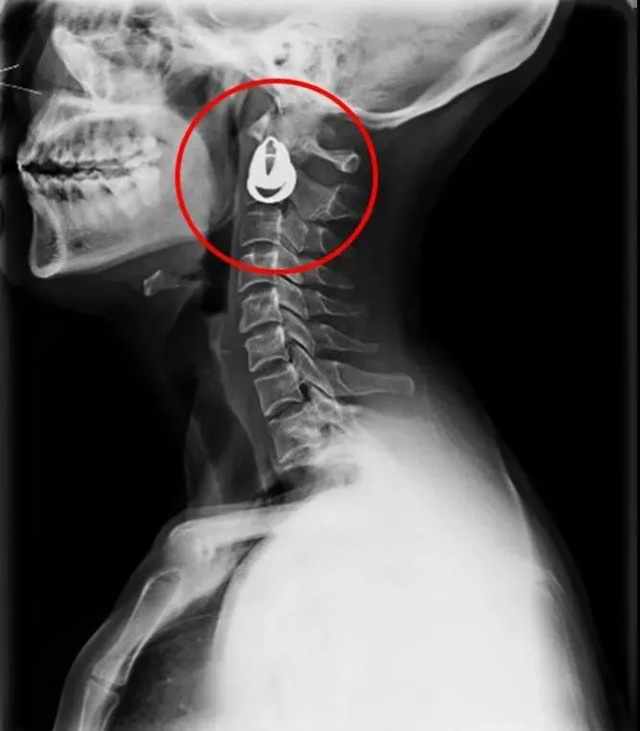

DR是一種比較常規(guī)的基礎影像學檢查方式,適用于人體各部位的健康普查及疾病檢查等優(yōu)勢,在臨床基礎檢查中備受醫(yī)生和患者的青睞。DR體檢車在健康體檢中有著非常重要的地位,由通過電纜串接在一起的探測板、掃描控制器、系統(tǒng)控制及影像顯示器等構成。對比CT檢查而言,DR檢查的價格更低,輻射劑量更小它可以讓疾病預防,微細病變可更好顯示診斷治療提供科學的結果依據。很多外傷患者都要做DR檢查,來判斷是否骨折或其他的情況。體檢過程中面對DR體檢車做檢查時候需要準備注意什么呢?很多時候大家都有這樣的疑問,身上攜帶的物品是否會對圖像造成遮擋或給機器帶來干擾?檢查前如何準備才不會影響檢查準確性?

首先需要穿比較寬松的衣物,不要戴金屬的飾品。還可以用醫(yī)院的衣服,胸圍的也要脫掉,因為有鋼圈。不然的話這些金屬飾品會干擾檢查圖像的清晰度,引發(fā)誤診或者漏診。半年內需要備孕懷孕的人士,應慎重或盡量避免放射線照射就需要跟醫(yī)生講,幼兒、年老體弱、危重患者,家屬應有效配合醫(yī)生完成檢查;對不用檢查的部位做好防護工作。在DR已經開始運作時候,檢查進行中的提示燈亮了,不要推開檢查室大門跟勿隨意進入,不然會受到輻射。按照醫(yī)生的要求保持好體位。曝光時候不動平靜均勻呼吸時屏氣,避免產生運動偽影這樣才能保障圖像的高清準確。